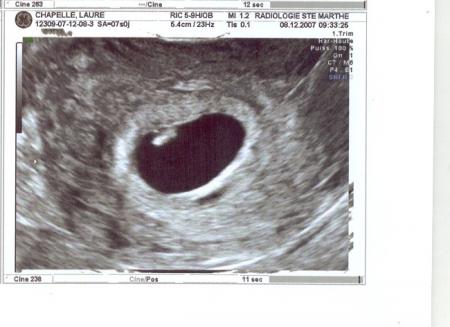

échographie de datation.

27/11/2008 19:46 par lauremanulucas

le 8 décembre 2007, maman apprend qu'elle est enceinte depuis le 5 novembre et que ma venue est prévue pour le 5 août 2008. c'est leur 1ère rencontre avec moi. oui oui c'est moi le petit trait blanc tout au dessus!!! 5,5 mm et 117 battements par minute. pour le poids il faudra revenir. impressionnant non???